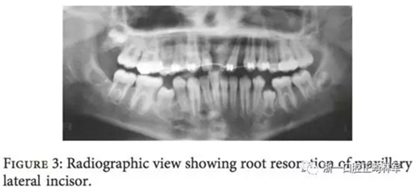

拉出上頜側(cè)切牙并恢復(fù)中切牙空間,然全景片提示上頜側(cè)切牙存在嚴(yán)重的牙根吸收因此選擇拔除(圖3)。